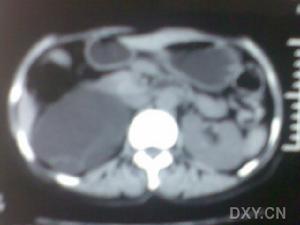

3.CT及磁共振(MRI)

有較高的診斷率。CT能提供膿腫的準確位置半顯示周圍臟器的關係。